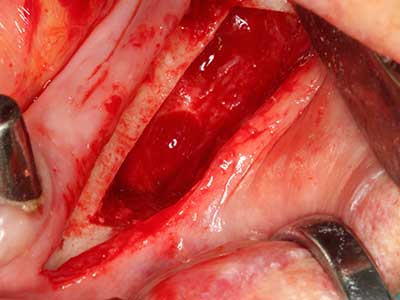

Bone tissue is not simply a mineral structure but also contains a substantial proportion of collagen fibres. This means it not only has good compressive strength but also a degree of flexibility, which can be taken advantage of when performing bone augmentations. In the classical expansion procedure using bone splitting, the atrophied alveolar ridge is split longitudinally and carefully expanded after reaching an adequate osteotomy depth (Fig. 13-16), ideally without substantial removal of the periosteum (Brugnami, Caiazzo et al. 2014, Stricker, Fleiner et al. 2014). Screw and plate systems with increasing expansion distance have proven effective in separating the two bone lamellae while remaining below the fracture threshold. In general, residual bone widths of at least 3–4 mm are required (Chiapasco, Zaniboni et al. 2006) to guarantee adequate flexibility and sufficient bone coverage of the future implants. If necessary, a vertical relief osteotomy on one or both sides can improve flexibility. A combination with additional augmentation techniques, particularly on the buccal side, has been described as an alternative to the classical technique.